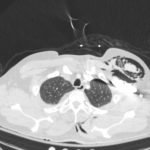

Plain film anteroposterior (AP) radiography of the chest shows left-sided subcutaneous emphysema (red arrow) with overlapping muscle striations of the pectoralis major (green arrow). After chest tube placement (blue arrow), AP chest radiography shows persistent left-sided subcutaneous emphysema (red arrow). CT of the chest shows pneumomediastinum (blue arrow), left apical pneumothorax (pink arrow), and subcutaneous emphysema (red arrow) at the level of T2. At the level of T6, rib fractures can be visualized on the CT (yellow arrow). At the level of T8, left sided pneumothorax is also seen (pink arrow) as the absence of lung tissue on CT.

Injuries of the thorax account for 25% of all mortality in trauma patients, of which many are preventable deaths by simple interventions.1,2 One sign commonly seen in patients with chest trauma is subcutaneous emphysema. The presence of this underlying emphysema has been suggested to be a sign of injury to the respiratory tract, making it clinically significant.3,4 Specifically, subcutaneous emphysema has been shown to be a clinical predictor of occult pneumothorax, with an odds ratio of 5.47.3 Furthermore, these injuries to the respiratory tract (pneumothorax /hemothorax, pneumomediastinum, etc.) can lead to hemodynamic instability and respiratory failure.4-6

In this patient, given the findings of multiple bilateral rib fractures, bilateral hemothorax/pneumothorax and multiple spine fractures, bilateral chest tubes were placed which had immediate output. The patient was admitted to surgical intensive care unit for chest tube management, pulmonary hygiene and further management of his other injuries.